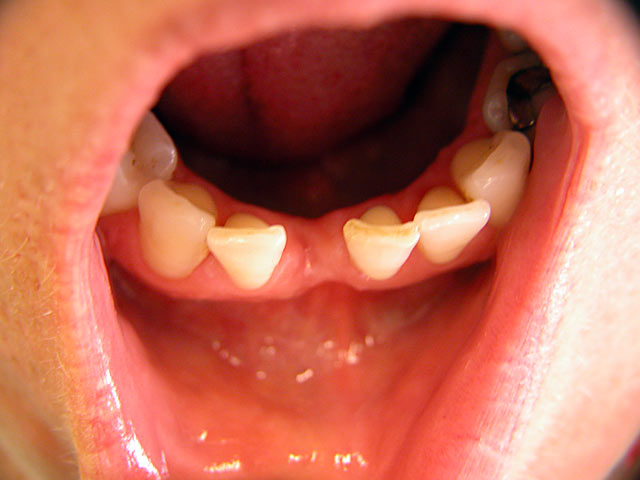

Kurzimplantate und Sofort – Implantate: